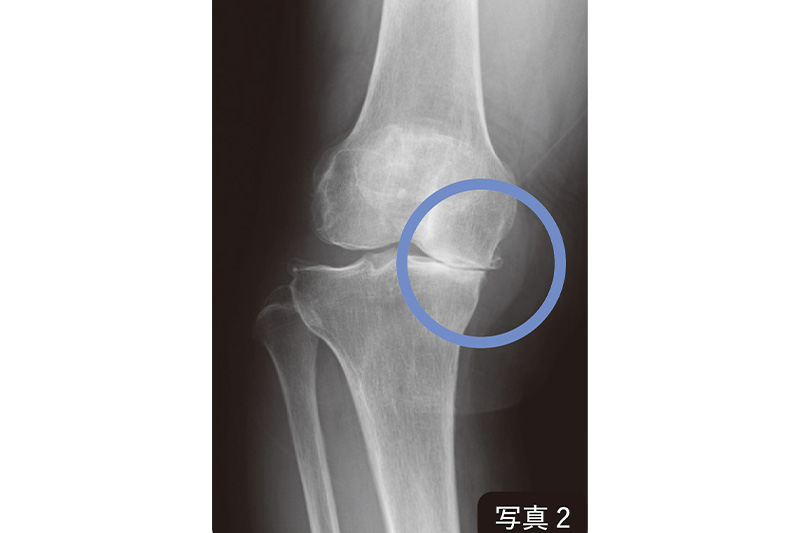

次に、もう1枚の別掲写真2を見てみましょう。中期の「変形性膝関節症」の人のひざを、立った状態でレントゲン撮影したものです。関節の中を見ても、内側の大腿骨と脛骨の間に隙間はありません。大腿骨と脛骨がほぼくっついてしまっています。

つまり軟骨は完全になくなってしまった。半月板の居場所もなくなっている。連続性を回復するには、元々の細胞が少しでも残っていることが必要です。しかし中期のこの患者さんの場合は、元々の硝子軟骨がほぼゼロ。連続性を回復させて、元の軟骨を再生させるのは難しい。Aパターンで治ることはかなり難しいということです。

しかし、この場合もからだの「治る力」を発揮させるセルフケアを行うと、代替えの軟骨(線維軟骨)ができ、痛みや歩行の問題が改善することが確認されています。これが代替えの線維軟骨によってひざ軟骨が復活するBパターンです。